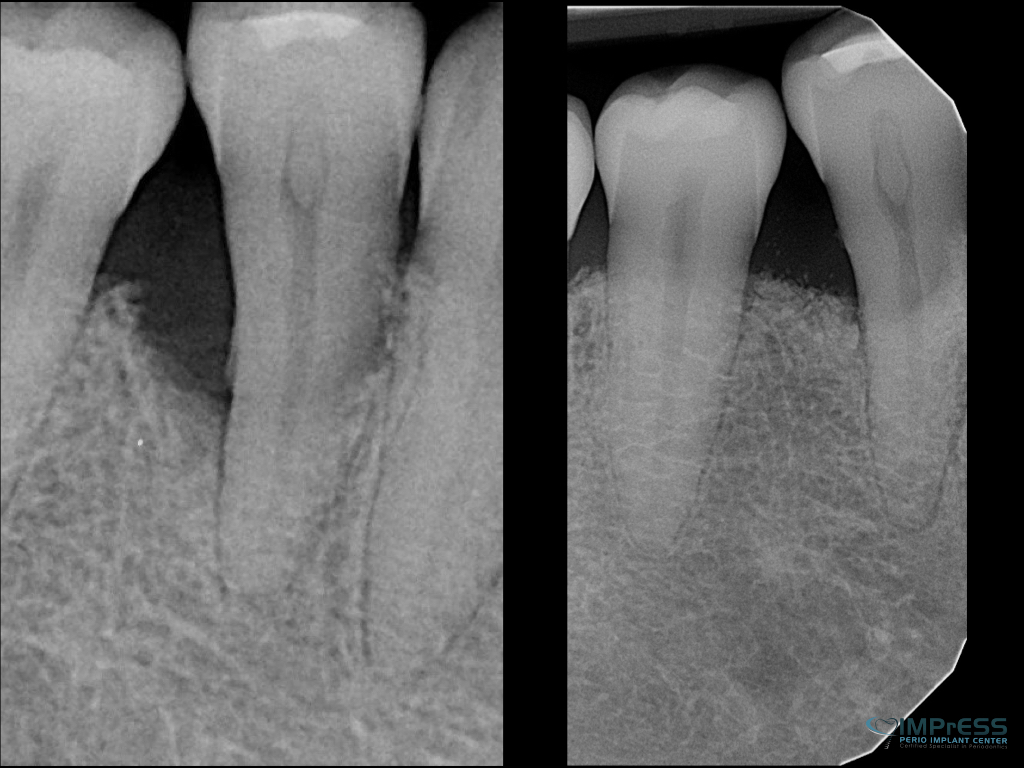

Before & Afters of Dental Implant Patients

Complete Dental Implant Cases Gallery

General Disclaimer: The results in the photographs are examples only and do not imply any certainty of the result of a procedure, and all outcomes are subject to the circumstances of the individual patient.